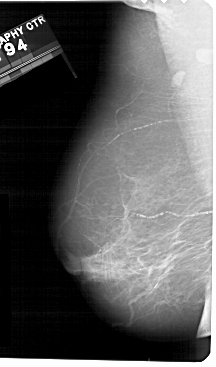

A_1357_1.LEFT_CC

RIGHT_CC LINES 5491 PIXELS_PER_LINE 2371 BITS_PER_PIXEL 12 RESOLUTION 43.5 OVERLAY

FILE: A_1357_1.RIGHT_CC.OVERLAY

TOTAL_ABNORMALITIES 1

ABNORMALITY 1

LESION_TYPE MASS SHAPE OVAL MARGINS ILL_DEFINED

ASSESSMENT 4

SUBTLETY 3

PATHOLOGY BENIGN

TOTAL_OUTLINES 1

BOUNDARY